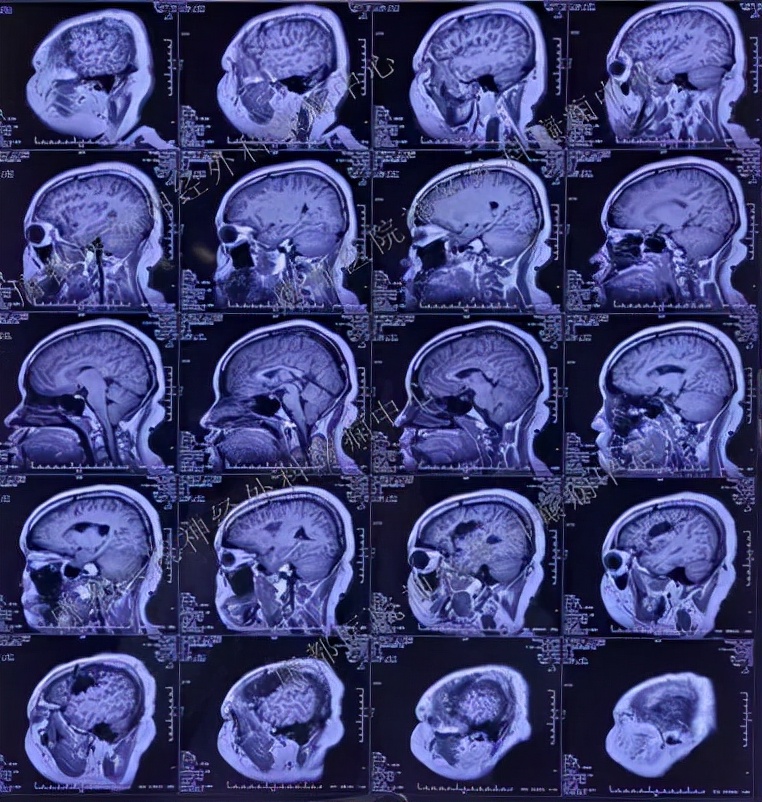

头颅MRI: